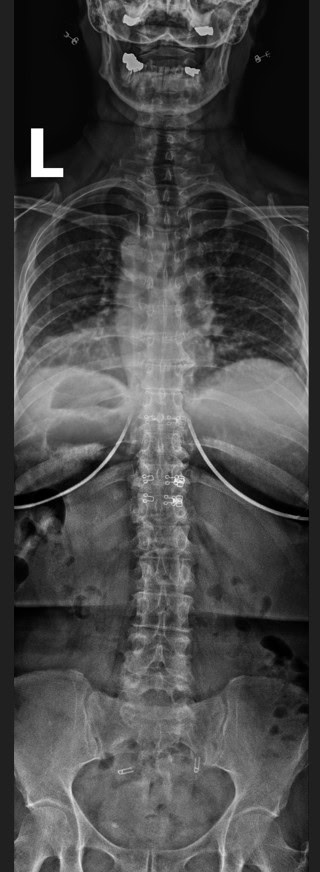

Pre Scan